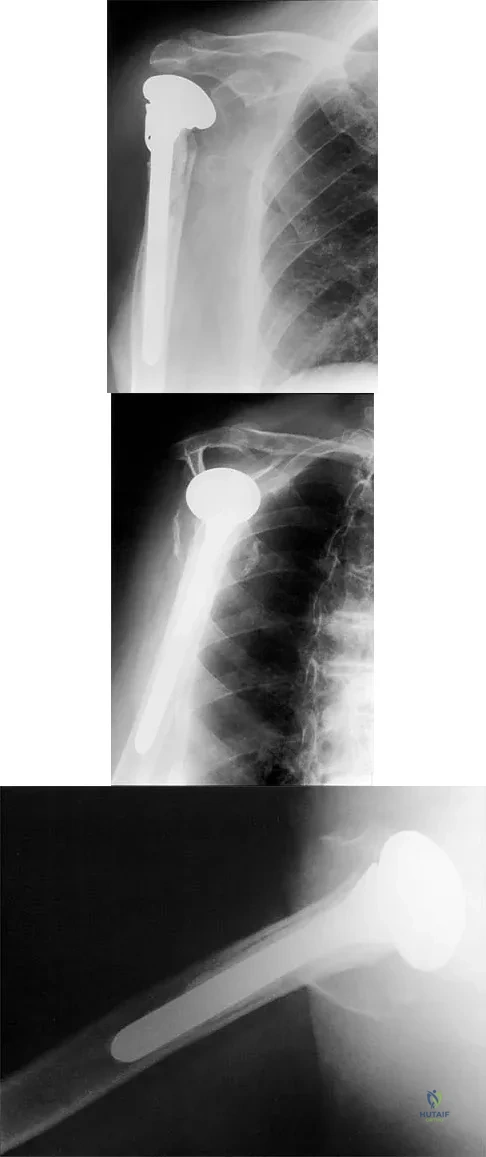

A 68-year-old woman has been progressing slowly after undergoing humeral head replacement for a four-part fracture 3 months ago. She has not regained active elevation, she feels an audible clunk on attempting elevation, and she reports pain and weakness. She used a sling for 2 weeks in the immediate postoperative period. Radiographs are shown in Figure 37a through 37c. Management should consist of

Explanation